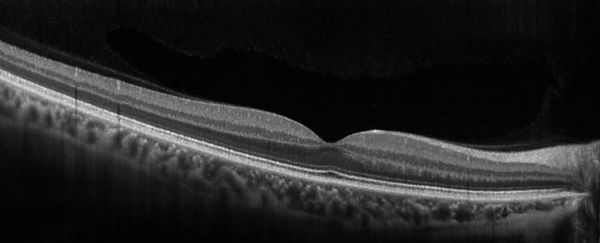

Estudio de OCT Macular: muestra alteración de la anatomía de la mácula por contracción de la membrana (línea blanca brillante)